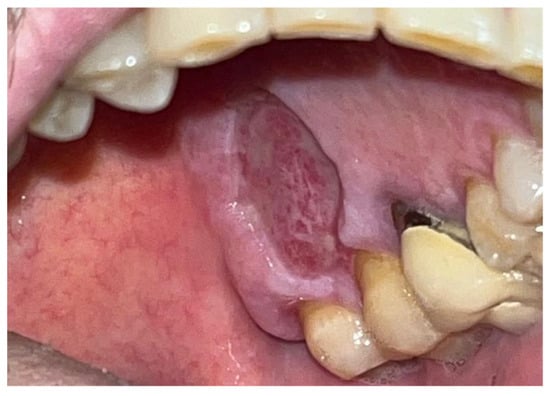

The study involved nine patients diagnosed with cardiovascular conditions, selected according to clearly defined inclusion criteria: presence of diagnosed cardiac conditions, the need for oral surgery, and signed informed consent. Exclusion criteria included patients with known allergies to the components of Glubran II, active infections, or systemic conditions contraindicating surgery. All patients were administered an antibiotic regimen consisting of Amoxicillin + Clavulanic Acid (875/125 mg), GlaxoSmithKlin, London, UK starting 24 h prior to the procedure, which was performed after obtaining cardiology clearance. Excellent results in terms of managing intra- and postoperative bleeding and tissue healing were observed in a 67-year-old patient with hypertension and diabetes mellitus, who underwent an excisional biopsy of a white lesion located on the palate with a leukoplakic appearance. The lesion, located on the palatal vault, appeared white, non-glossy, with undefined margins and soft consistency, and was non-removable via scraping biopsy (Figure 1 and Figure 2). A decision was made to surgically remove the lesion with wide incision margins to provide a biopsy sample (containing the lesion with surrounding healthy tissue) to the Department of Pathological Anatomy at the University Hospital of Rome Tor Vergata.

Figure 1. Lesion resembling leukoplakia localized on the palate, non-removable through biopsy by scraping.

Figure 2. Leukoplakia-like lesion localized on the palate following scraping with a sterile gauze.